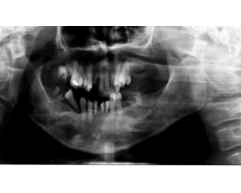

重度の歯周病により、歯を支える骨がほとんど溶けてしまっており、歯がグラグラとなり咬み合わせが大きく崩れている。

家でいう大黒柱が1本もない状態である。

吉本歯科医院では、口内写真とパノラマレントゲンを撮影し、まずは顎の骨の状態まで詳しく確認しました。